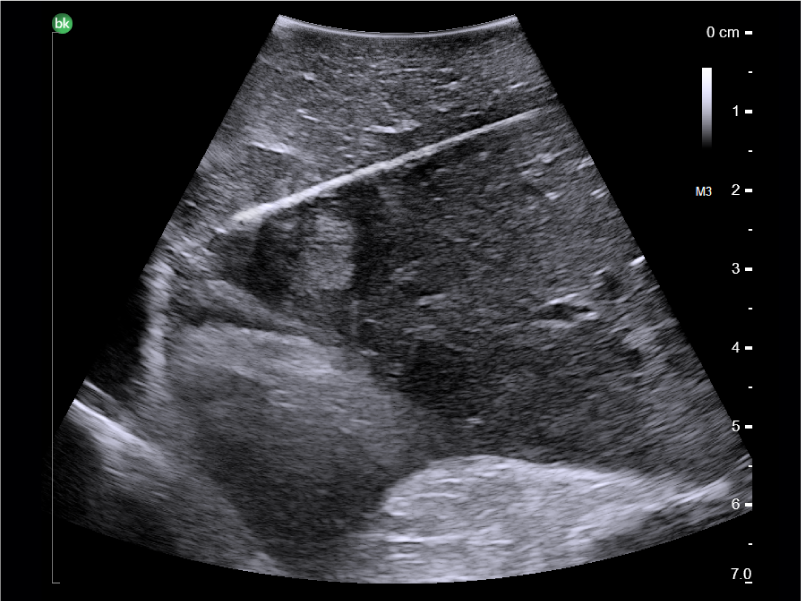

Liver metastatic lesion, ablation procedure, visualized with Laparoscopic Transducer

Liver mass, post-ablation, visualized with Advanced Laparoscopic Transducer

• Guide and view needle placements in real-time.